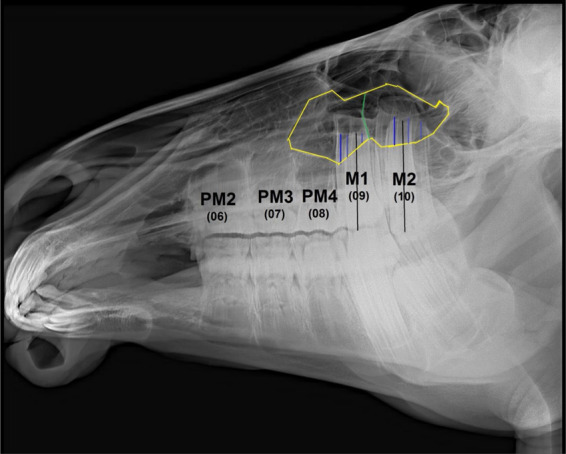

Dareshuri马是伊朗法尔斯省的主要品种。虽然影响上颌颊齿和上颌窦的疾病相对常见,但关于这些结构在不同年龄的尺寸和关系的基础数据有限。考虑到年轻马的头部在成熟过程中发生了显著的解剖学变化,本研究旨在评估上颌颊齿在吻侧和尾侧鼻窦(分别为RMS和CMS)内的位置和解剖关系的年龄相关变化,以及在其生长过程中单个鼻窦室的长度和高度的变化。研究人员对29匹年龄在4个月至5岁之间的健康活马的头部进行了放射线照相,并使用EConsole1放射线照相查看器软件(V.3, 2017, DRTECH Europe GmbH, Schwalbach am Taunus,德国)进行了分析。统计分析显示,整个研究中唯一显著的变化是CMS长度的增加(4.075±0.99 cm; SE),这在3岁以下的马中更为显著。在不到1岁时,上颌窦中唯一存在的牙齿是M1。1 ~ 2岁时,M2进入上颌隔室;PM4在2 ~ 3岁进入RMS, M3在3 ~ 4岁进入CMS。最终,在4 ~ 5岁时,PM3、M1和M2出现在RMS中,M2和M3出现在CMS中。本研究结果对临床上颌面部疾病的诊断和治疗具有一定的参考价值,并可作为进一步解剖研究的参考。

Dareshuri horses are the predominant breed in Fars Province, Iran. Although disorders affecting their maxillary cheek teeth and maxillary sinuses are relatively common, limited fundamental data are available on the dimensions and relationships of these structures at different ages. Given the significant anatomical changes in the heads of young horses as they mature, this study aimed to evaluate age-related changes in the position and anatomical relationships of individual maxillary cheek teeth within the rostral and caudal maxillary sinuses (RMS and CMS, respectively), as well as changes in the lengths and heights of individual sinus compartments during their growth. Radiographs were performed on 29 heads of live, healthy horses aged between 4 months and 5 years and were analyzed using the EConsole1 Radiography Viewer software (V.3, 2017, DRTECH Europe GmbH, Schwalbach am Taunus, Germany). Statistical analyses revealed that the only significant change throughout the study was an increase in the length of the CMS (4.075 ± 0.99 cm; SE), which was more significant in horses up to three years old. At less than 1 year old, the only tooth present in the maxillary sinus was M1. At 1-2 years old, M2 was observed entering the maxillary compartments; PM4 entered the RMS at 2-3 years old, and M3 entered the CMS at 3-4 years old. Eventually at 4-5 years old, PM3, M1, and M2 were present in the RMS, and M2 and M3 were present in the CMS. This information should be of value in the diagnosis and treatment of Dareshuri maxillofacial disorders and used as a reference for further anatomical investigations.